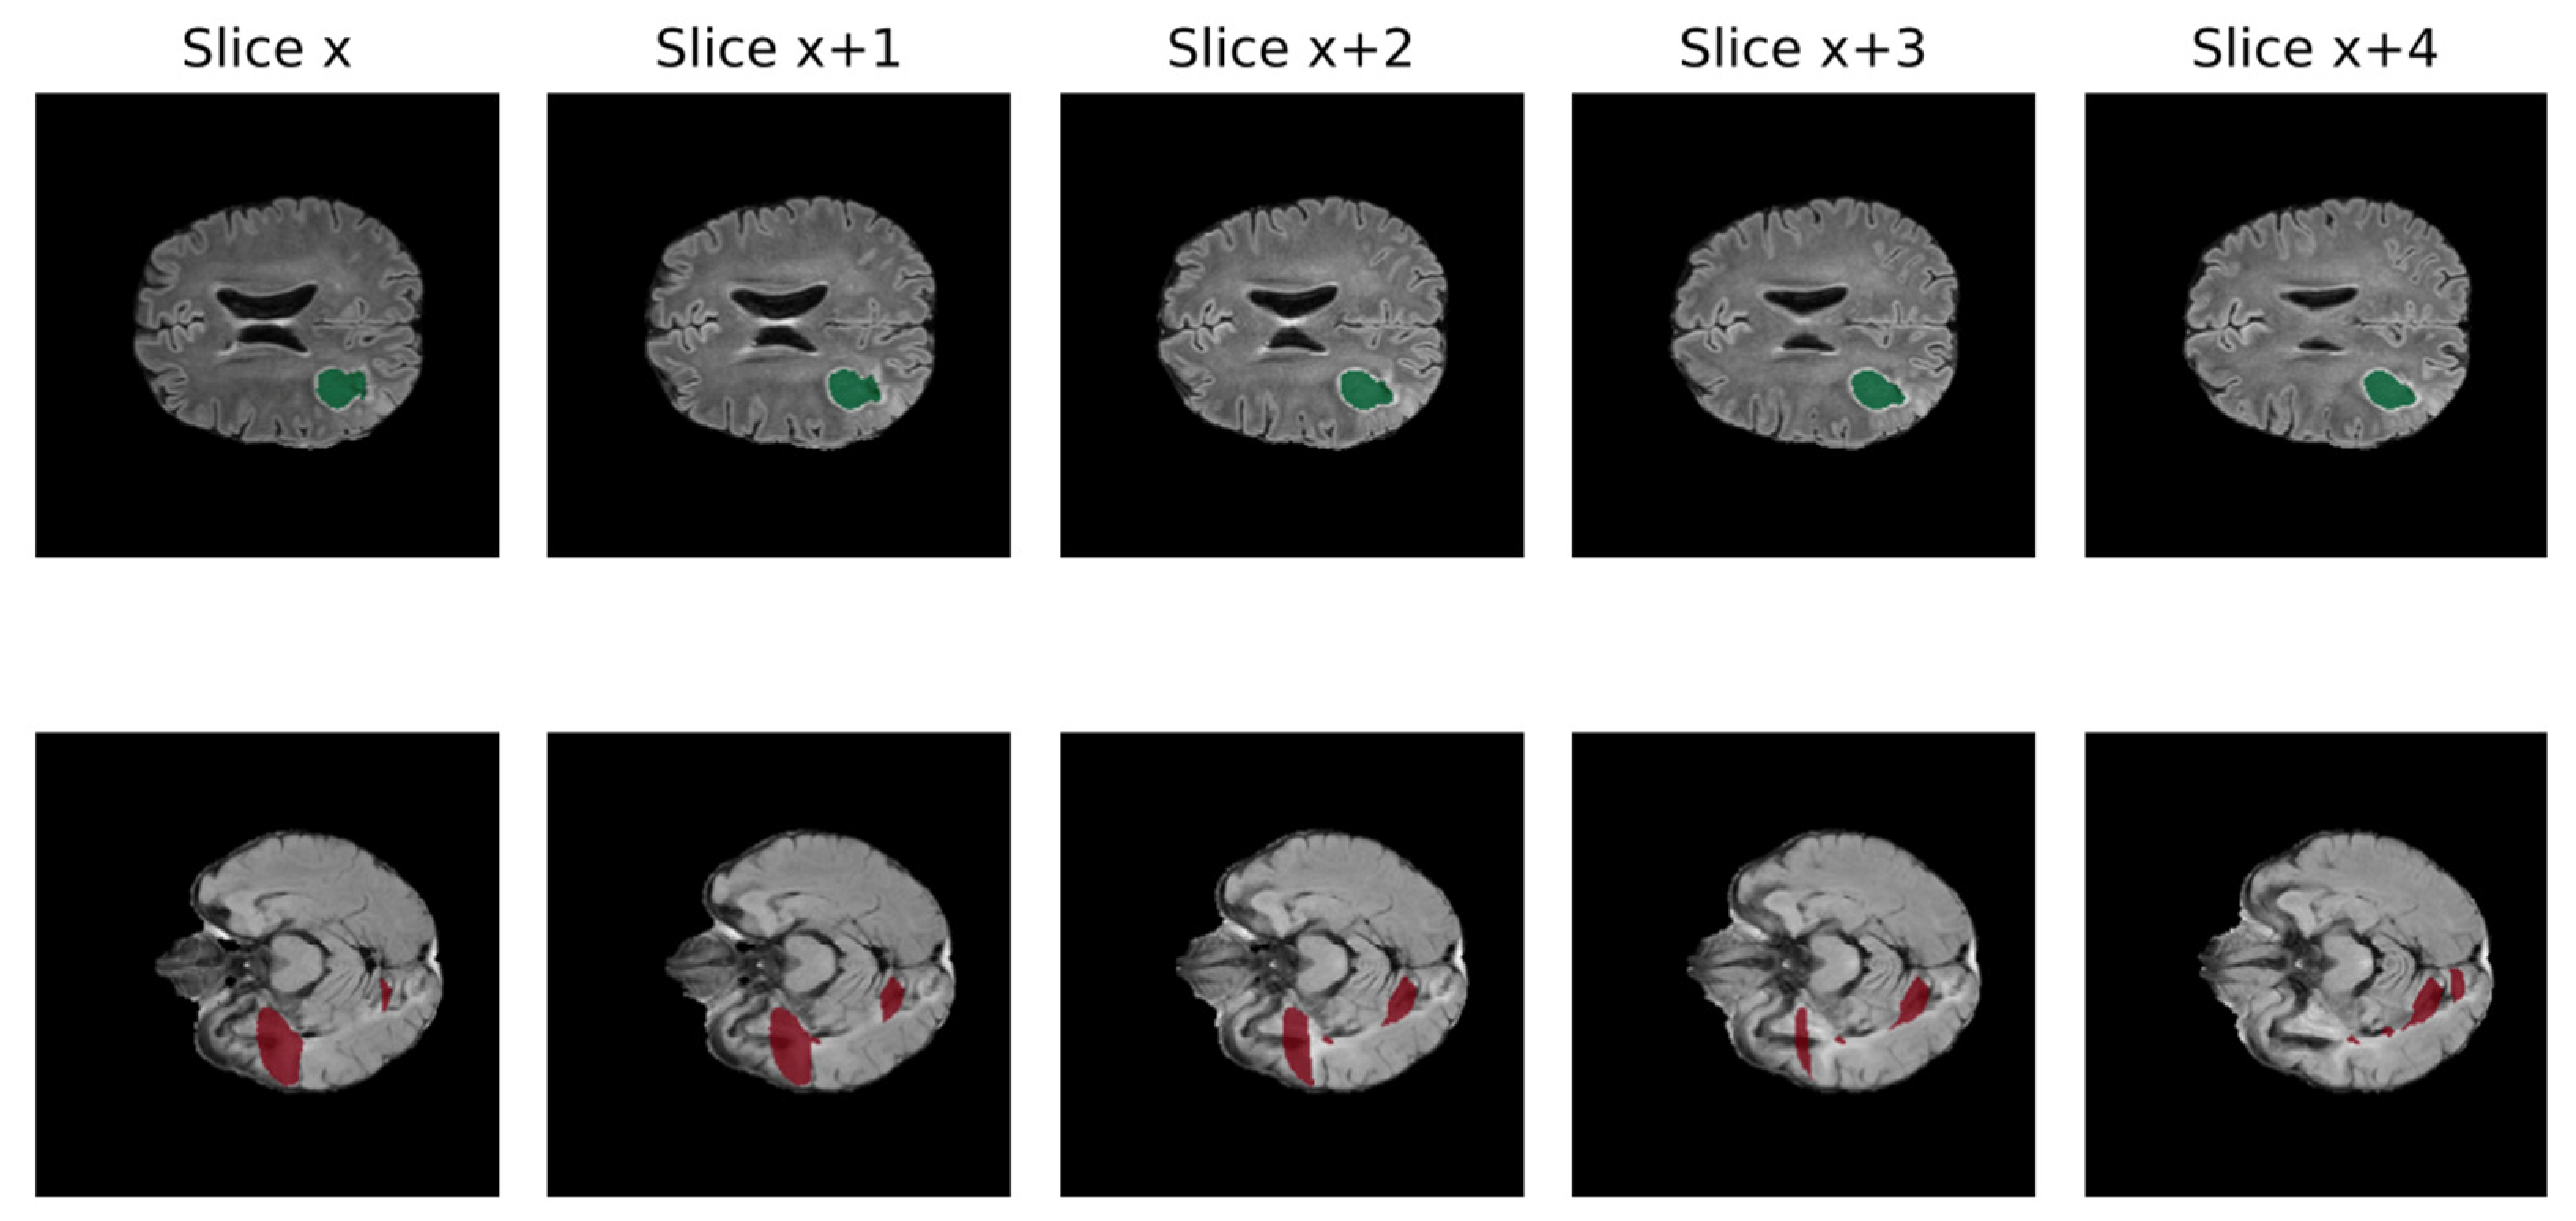

3.2. Data Quality

A significant obstacle to the efficient growth of AI application in clinical practice is data quality. AI models require large amounts of high-quality images to obtain reliable results, whereas medical data frequently present suboptimal qualities for this task [61]. In fact, suboptimal quality of data is very common in clinical practice, including non-volumetric scans, missing sequences, and artifacts [62]. Low quality may negatively impact the performance because real inter-image variability results are hardly distinguishable from artifacts. In Figure 3, the non-volumetric image negatively affected the result of the segmentation from a DL-based algorithm [47].

Figure 3.

Qualitative comparison of processed FLAIR from volumetric raw input (above) and non-volumetric one in 5 different slices of the same MRI (Green: cavity, Red: FLAIR hyperintensity) [46].